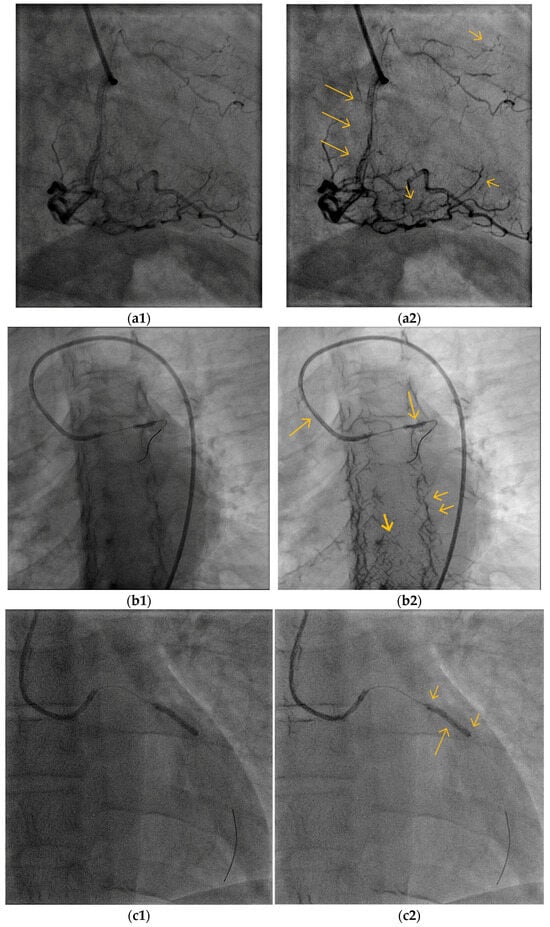

5.1. Overall Visibility Enhancement

5.2. Blood Vessel Interiors

5.3. Small Blood Vessels

5.4. Low-Contrast Agent, Low-Radiation, and No Contrast Agent